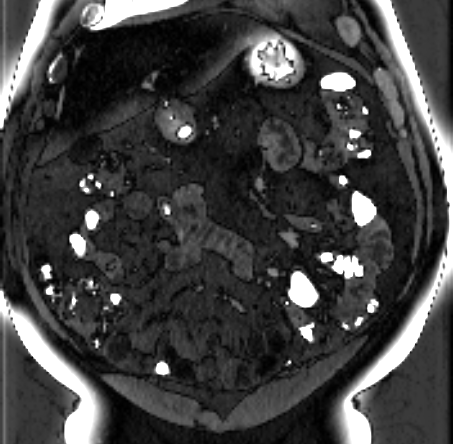

Figure 3 shows example segmentation results in 3D. The result corresponding to ‘feat. & out. level DA’ in Table 1 is compared to ours. We note that the only difference between them is whether the feature disentanglement is involved for the domain adaptation, thus could show its effectiveness. Fewer errors are observed for the proposed method. We believe this is because the proposed method explicitly concentrates on the features more transferable across the datasets, the non-intensity features in this work, by disentangling those features and applying adversarial learning directly to them during the adaptation process. Example reconstruction results from the auto-encoding architecture as well as segmentation results in coronal view can be found in supplementary material.

A

B

B

C

C